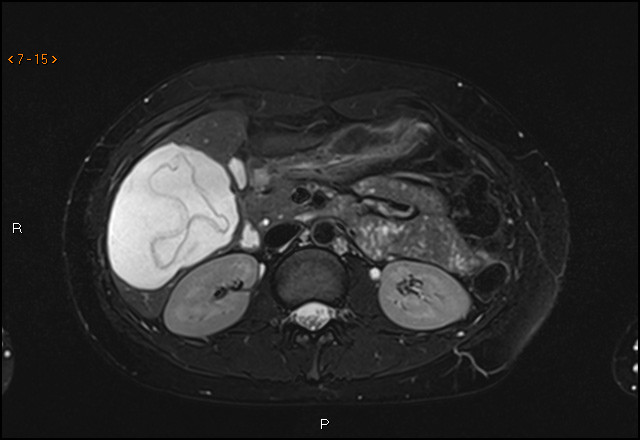

Ultralydundersøkelsen viste en cyste i leveren. Største diameter var 10 cm. Den hadde en foldet indre struktur, forenlig med en separat, flytende indre membran, såkalt vannliljetegn. Dette funnet er karakteristisk for ekinokokkcyste. Pasienten ble henvist videre til infeksjonsmedisiner. Serologiske prøver var også positive for ekinokokker.

Diagnosen stilles på bakgrunn av typiske bildefunn og antistoffundersøkelse. For å avdekke om det foreligger kompliserende forhold (som rumpert cyste eller fisteldanning til galleveiene) bør cysten også utredes med MR- eller CT-undersøkelse (2). Verdens helseorganisasjon (WHO) har utgitt en ultralydbasert klassifikasjon av ekinokokkcyster, og behandlingen bestemmes ut fra WHO-klassifikasjonen og cystens størrelse (2, 3). Behandlingen består enten av observasjon eller medikamentell behandling med albendazol – alene eller i kombinasjon med aspirasjon og reinstallasjon av parasittdrepende middel (f.eks. hypotont saltvann eller etanol) – eller kirurgisk ekstirpasjon av hele cysten.